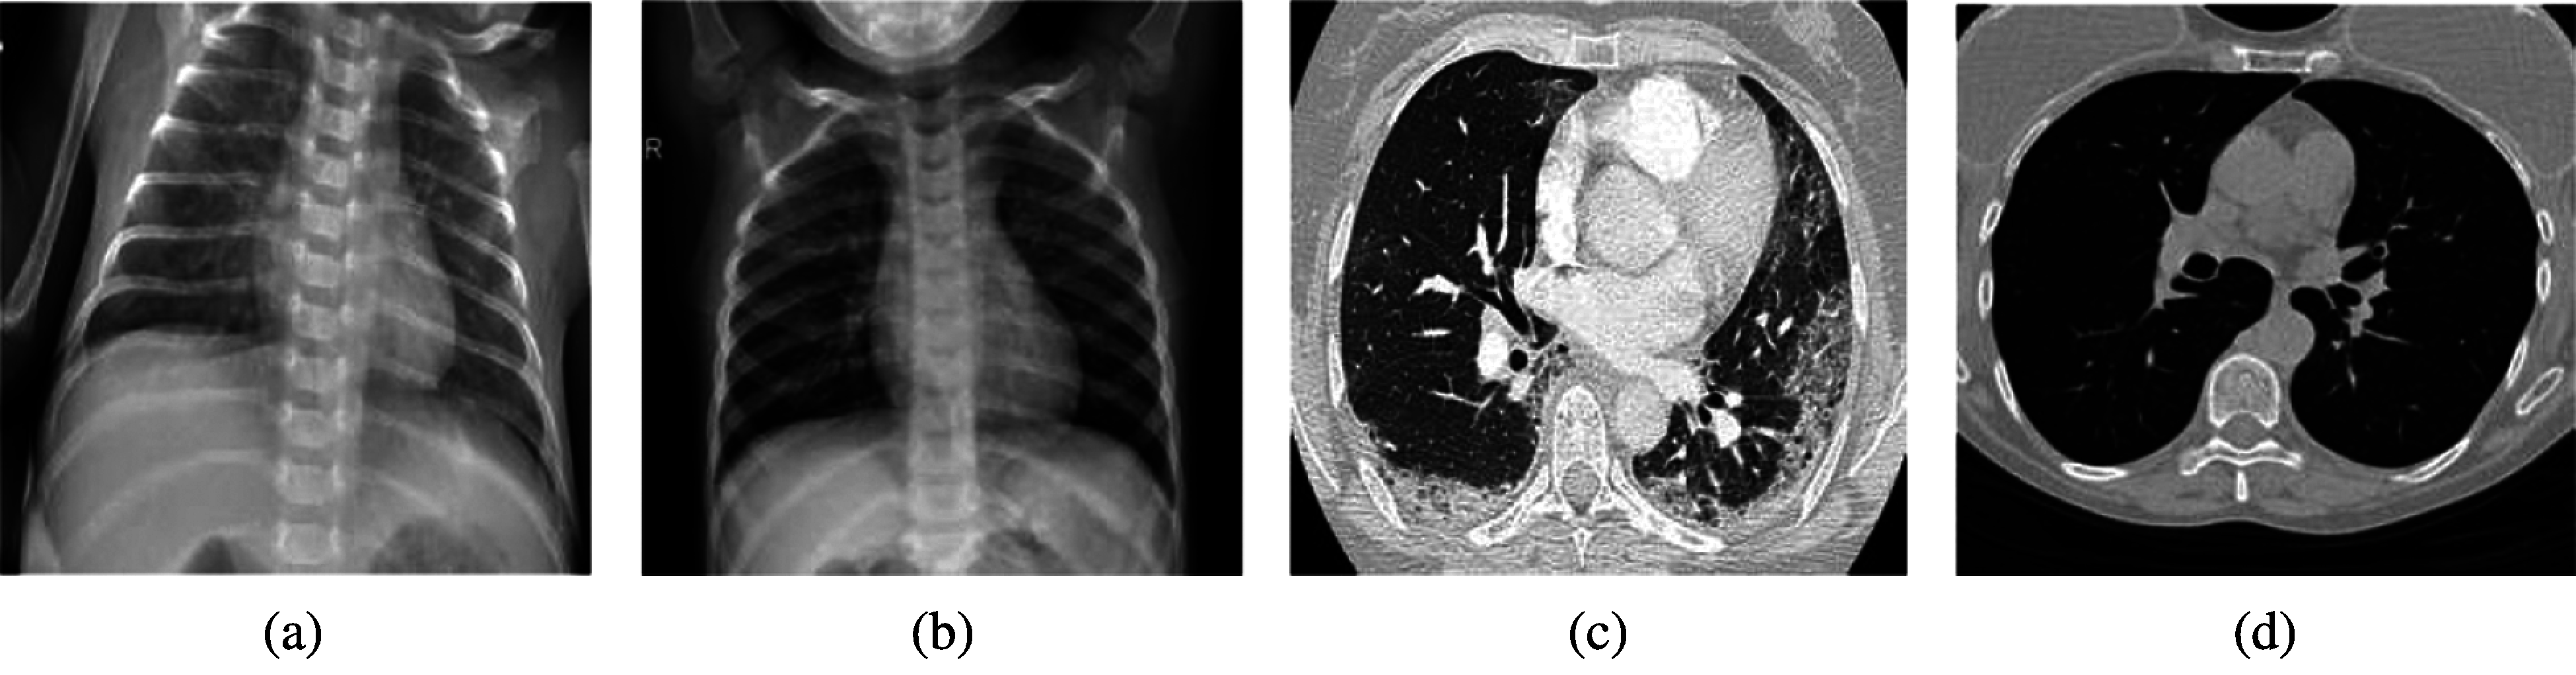

The dataset is divided into a 70% training set and a 30% validation set. The partitioned datasets of the training and testing help in data cross-validation. The cross-validation checks whether the suggested classifier precisely classifies the normal vs. COVID-19 images or not. A sample of employed datasets is shown in Fig. 1.

Figure 1: Samples of CXR and CT COVID-19 and non-COVID-19 images (a) CXR COVID-19 images (b) CXR non-COVID images (c) CT COVID-19 images (d) CT non-COVID images